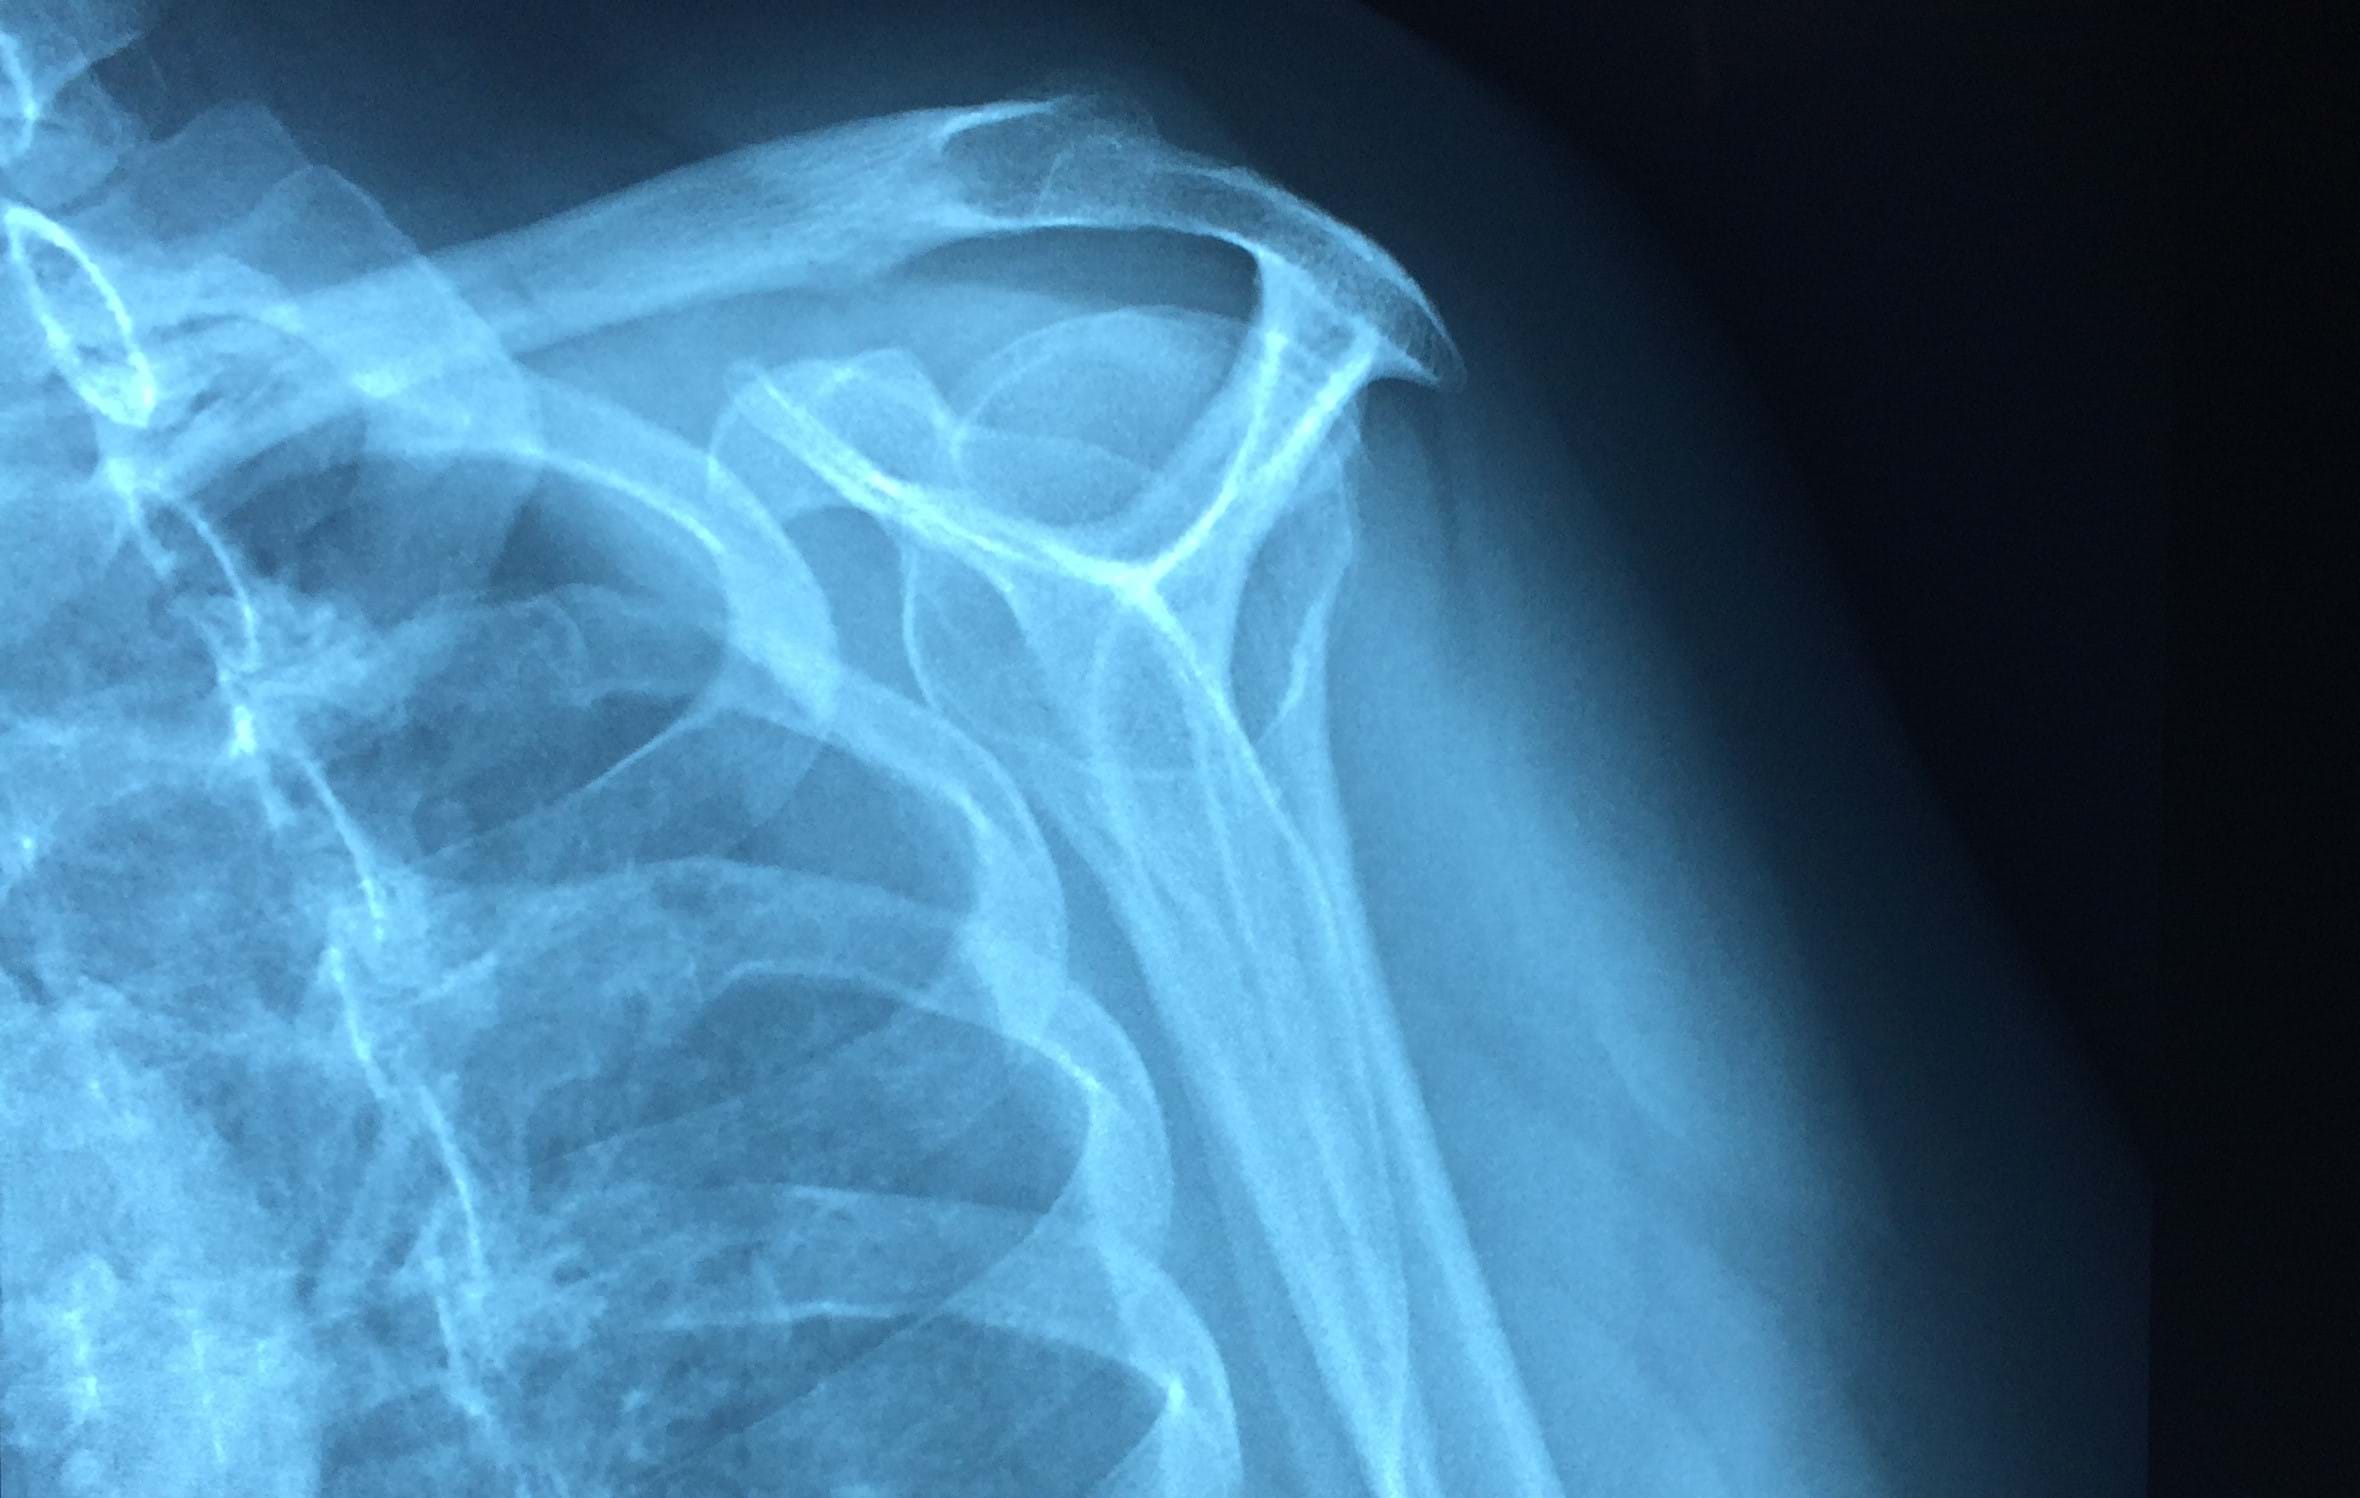

Weight training has become one of the most popular forms of exercise in recent years, though shoulder pain whilst lifting weights is very common for some people. There are many structures in the shoulder joint that can be the source of your pain and this blog explores the list, and explores some solutions for you shoulder pain from the gym.

For those exploring solutions, shoulder arthroscopy and subacromial decompression are common procedures that offer certain people, with certain conditions, often great relief.